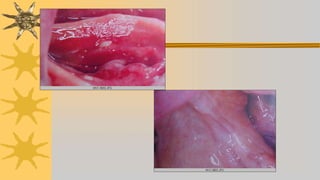

Utilizar silicona fluida aplicada sobre base

Fit checker silicona mas fina

Pastas indicadoras de presión , polvo de oxido de cinc

Pasta reveladora, cera muy blanda , color blanco

Lo que debemos de conseguir con cualquiera d eestos

materiales es verificar zonas donde el material sea

transparente o capas muy delkgadas, significará que esta

haciendo presion y hay que aliviar